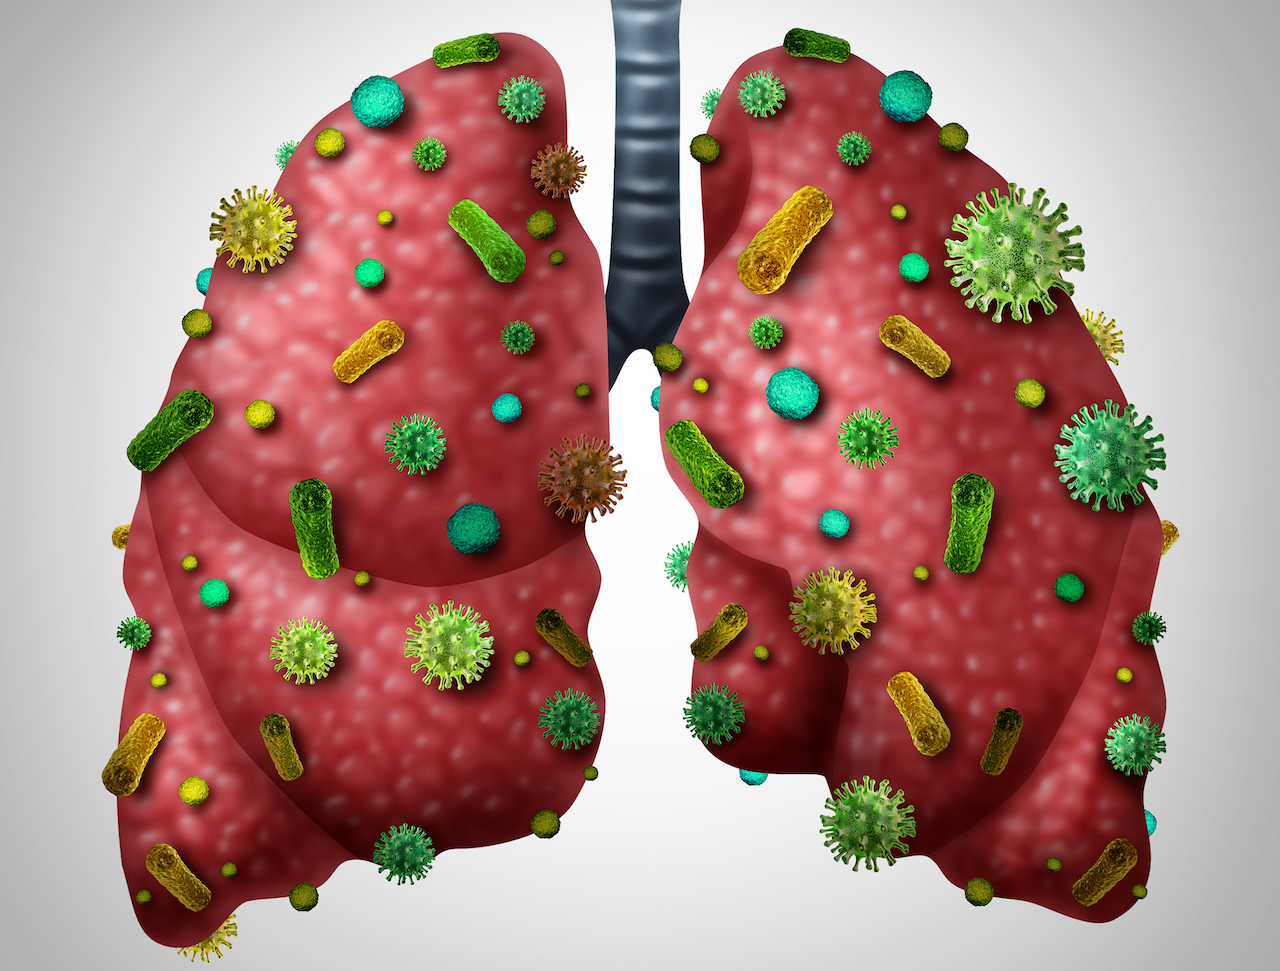

Фотографии бактерий, вызывающих бактериальные пневмонии у животных

Раздел: Другие животные